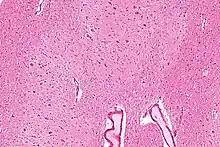

Micrograph of the dentate nucleus (pale pink). H&E stain.